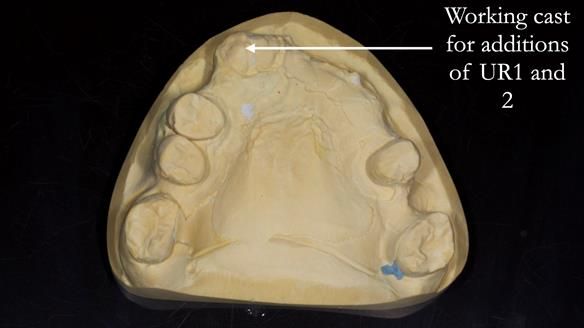

- Add upper right lateral and central incisor denture teeth to existing upper RPD as temporary measure during making of new RPDs